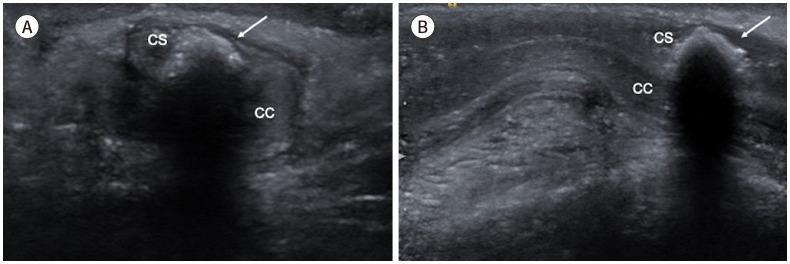

Penile emergencies are uncommon and can be categorized as having infectious, vascular, traumatic, or multifactorial etiologies. To facilitate early diagnosis and treatment during emergency, US and color Doppler imaging are imperative. US depicts hypoechoic collections regardless of the presence of air foci in infections like abscess and Fournier's gangrene. Color Doppler imaging is conducted to evaluate vascular conditions such as penile Mondor disease (PMD) and priapism. PMD is indicated by the absence of color flow and non-compressibility of dorsal penile vein. Priapism can be categorized based on cavernosal artery flow: high flow and low flow. In traumatic injuries like penile fracture, US reveals breach in tunica albuginea with hematoma. Peyronie's disease can be multifactorial in origin and the imaging is commonly visualized as thickening of the tunica albuginea and echogenic calcified plaques. Urethral injuries are urethral discontinuity with adjacent collection. Urethral calculus is visualized as echogenic focus with posterior acoustic shadowing. Therefore, effective collaboration between radiologists and urologists is required for appropriate initial diagnosis and prompt treatment.

阴茎急症并不常见,可分为感染性、血管性、创伤性或多因素病因。为便于在急诊时进行早期诊断和治疗,超声(US)和彩色多普勒成像必不可少。在诸如脓肿和福尼尔坏疽等感染中,无论是否存在气灶,超声均能显示低回声液性聚集。进行彩色多普勒成像以评估血管状况,如阴茎蒙多氏病(PMD)和阴茎异常勃起。阴茎蒙多氏病表现为阴茎背静脉无血流信号且不可压缩。阴茎异常勃起可根据海绵体动脉血流分为:高流量型和低流量型。在阴茎骨折等创伤性损伤中,超声显示白膜破裂并伴有血肿。佩罗尼氏病的病因可能是多因素的,影像学表现通常为白膜增厚和回声增强的钙化斑块。尿道损伤表现为尿道连续性中断并伴有相邻液性聚集。尿道结石表现为伴有后方声影的回声增强灶。因此,放射科医生和泌尿外科医生之间需要有效协作,以进行恰当的初步诊断和及时治疗。